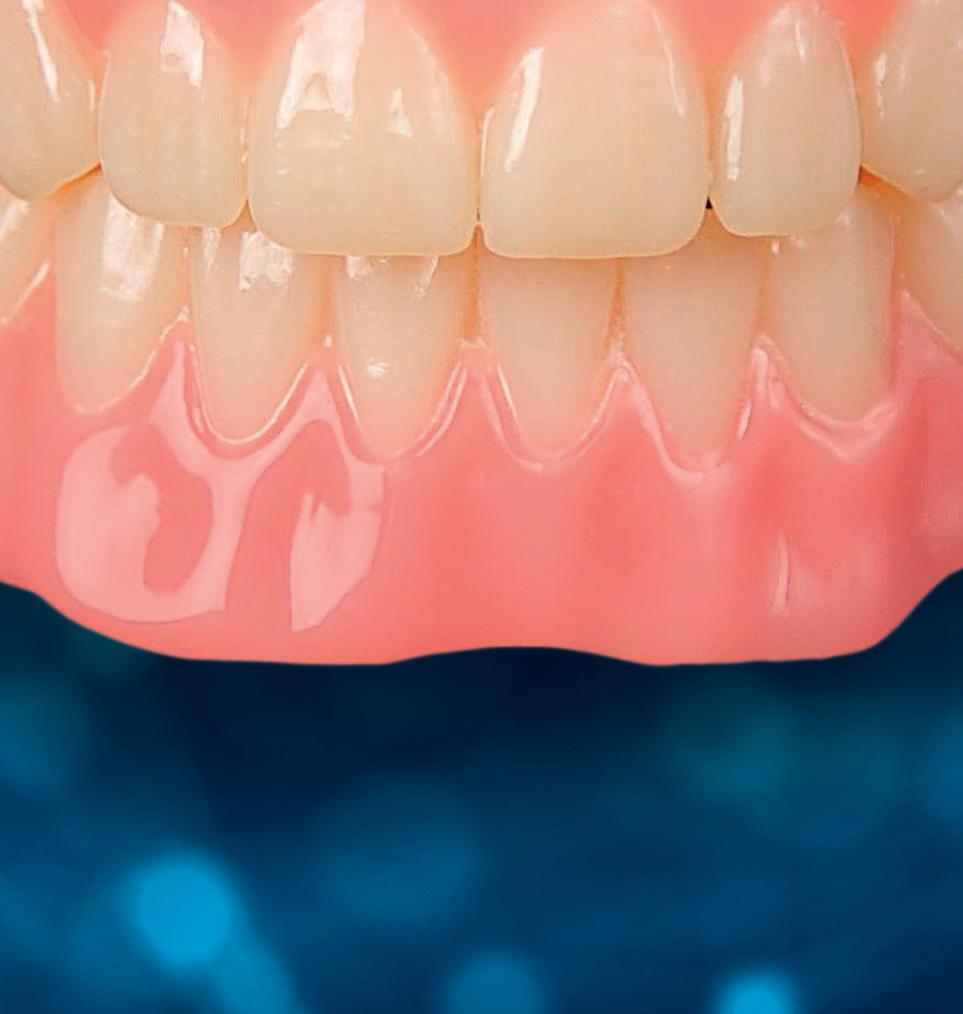

Een 47-jarige vrouw wordt aan het einde van het orthodontische traject door haar eigen tandarts naar mij verwezen voor een intake en eventuele behandeling. Bij mevrouw zijn elementen 12 en 22 afwezig. De 13 en 23 zijn gemesialiseerd. Haar eigen tandarts vraagt of ik het front met composiet kan restaureren om weer een harmonieuze glimlach te krijgen (Afbeelding 1).

Tijdens de intake wordt een complete lichtfoto status gemaakt om de positie van de elementen goed in kaart te brengen en een behandelplan op te kunnen stellen. Op de close-up foto van het bovenfront (afbeelding 2) zien we dat er sprake is van slijtage aan element 11. Elementen 12 en 22 zijn afwezig en elementen 13 en 23 zijn gemesialiseerd. Tussen element 11 en 13 is er sprake van een diasteem. Dit diasteem is niet aanwezig aan de andere zijde (afbeelding 3).

Nadat de vaste apparatuur verwijderd is (afbeelding 7 en 8), zie ik mevrouw voor het maken van een afdruk/scan ten behoeve van een wax-up. Aangezien ik in deze casus wil werken met de injectietechniek, is een wax-up noodzakelijk.

Voor een wax-up ten behoeve van opbouw met composiet worden strengere eisen gesteld dan aan een motivational wax-up. Wanneer je de wax-up wil gebruiken voor het overzetten met composiet, is het belangrijk om een nauwkeurige transparante mal te hebben (Exaclear, GC). Deze mal moet transparant zijn om voldoende licht van de polymerisatielamp door te laten om zeker te weten dat al de composiet goed uithardt. Verder is het belangrijk om te weten dat Exaclear een ontzettend nauwkeurig materiaal is. Dit houdt in dat je een exacte kopie zult maken van de wax-up. Alle foutjes en oneffenheden in de wax-

up zullen dus ook overgezet worden in de mond. Om de situatie van de wax-up zo goed mogelijk om te zetten in de mond is het daarnaast belangrijk dat je mal voldoende afsteuning heeft. Dit kun je doen door sommige elementen of delen daarvan niet te laten opwassen (in dit geval de palatale zijde van de elementen).